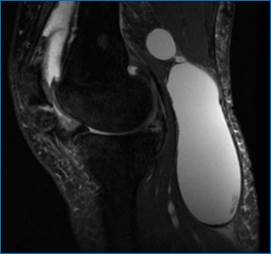

Рис. 5. Киста Бейкера (МРТ- картина разрыва капсулы)

В то время как крупная киста, киста с разрывом капсулы (рис. 4,5) может клинически имитировать острый тромбоз вен нижней конечности.